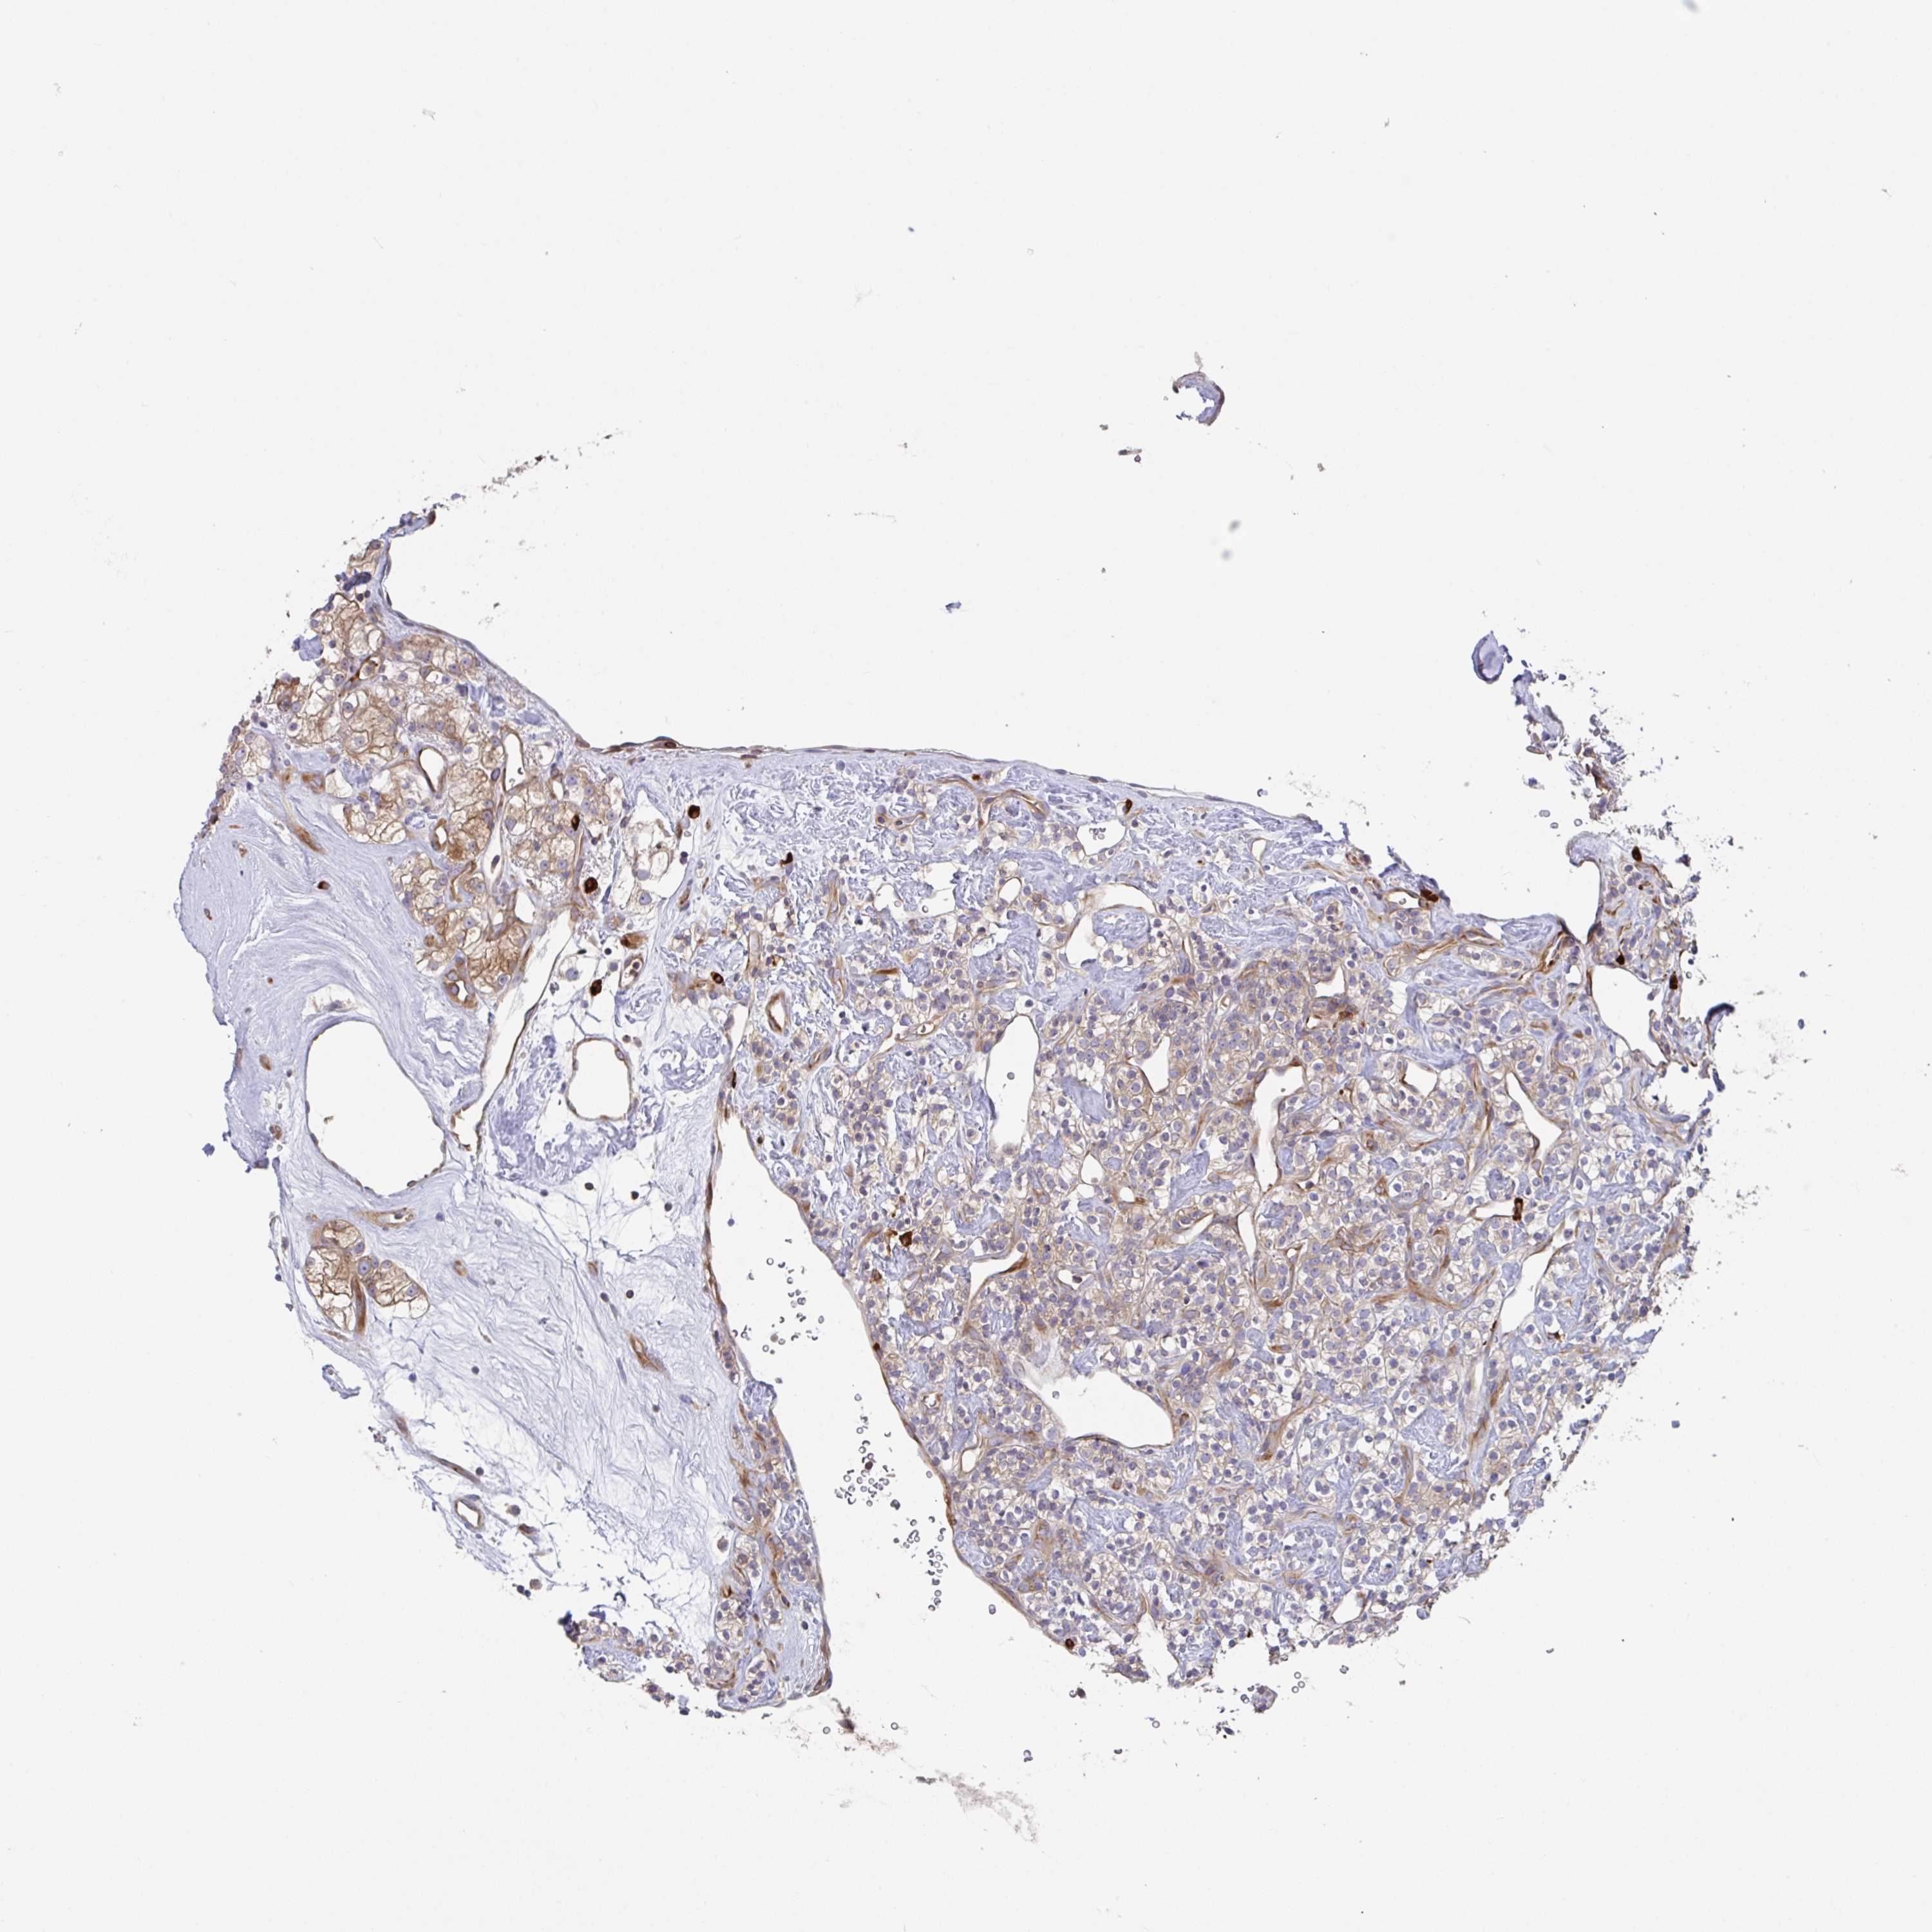

CANCER RENAL CANCER Show tissue menu

KICH TCGA KIRC TCGA KIRC VALIDATION KIRP TCGA PROTEIN RCC CPTAC PROTEIN EXPRESSION